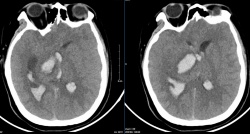

Đến 14 giờ, bệnh nhân được vận chuyển đến đảo Trường Sa để cấp cứu trong tình trạng tỉnh, tiếp xúc tốt, yếu nửa người phải, sức cơ 3/5, giảm cảm giác người.

Qua thăm khám, các bác sĩ chẩn đoán bệnh nhân bị đột quỵ não theo dõi xuất huyết bán cầu T và tiến hành các biện pháp cấp cứu.